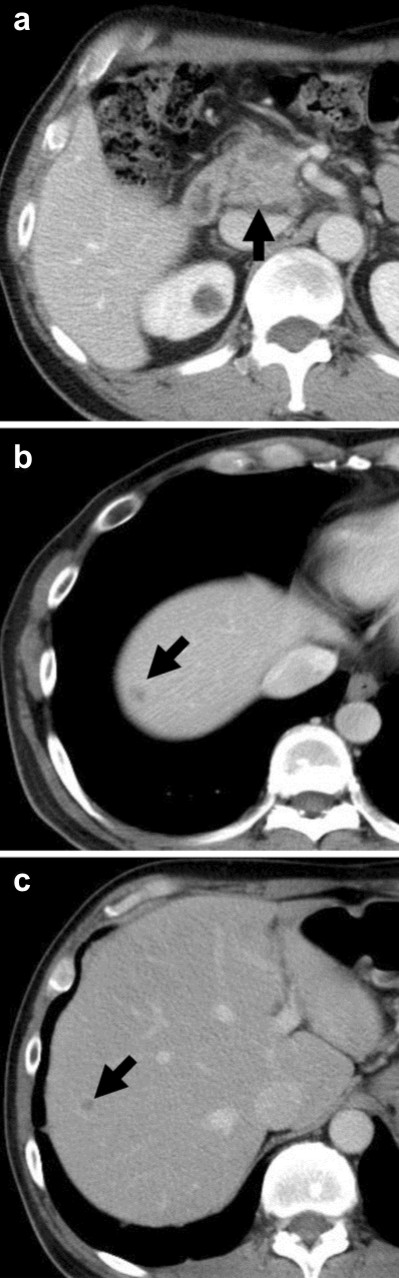

A fifty-five-year-old male had been admitted to our hospital for pancreatic cancer. He was not a smoker and had no history of pulmonary disease. An abdominal computed tomography (CT) scan revealed a tumor measuring 30 mm in diameter at the head of the pancreas (Figure 1a) with multiple liver metastases (Figure 1bc). He was treated with gemcitabine in combination with erlotinib. Gemcitabine was administered with a protocol of 1,000 mg/m2 weekly for 3 weeks followed by 1 week rest. Erlotinib was administered with a protocol of 100 mg/body every day. One week after starting erlotinib, he developed a skin rash - mainly affecting the face and neck - which was controlled by oral minocycline without worsening. On the 13th day of erlotinib treatment, he presented with a fever elevated up to 40 degrees. No clinical focus of infection was found. Vital signs were stable, white blood cell (WBC) count was within normal limits (6,400 µL-1; reference range: 0-9,000 µL-1), and C-reactive protein (CRP) was slightly elevated (1.98 mg/dL; reference range: 0-0.1 mg/dL). On the next day, the high fever continued and WBC count elevated to 11,800 µL-1. CRP level was also elevated to 16.09 mg/dL. The percentage of blood eosinophil was within normal limits (1%; reference range: 2–6%). Serum KL-6 level was within normal limits (448 U/mL; reference range: 0-499 U/ml). Chest X-ray revealed reticular shadow in the bilateral lung fields. Chest CT scan showed a diffuse ground-glass like infiltration of both lungs without any sign of pulmonary edema or pleural effusions (Figure 2ab). He was diagnosed with ILD, and a high-dose corticosteroid with an antibiotic agent therapy was introduced. Prednisolone was applied with an initial dose of 1,000 mg/day for 3 days and an antibiotic agent was also applied for 3 days. After that, the reticular shadow was reduced gradually on CT. Following a high-dose corticosteroid pulse therapy, prednisolone was applied for internal use with a dose of 60mg/day. Two weeks after the introduction of steroid therapy, the ILD faded away on CT (Figure 2cd). The dose of corticosteroid was gradually decreased by half every 2 weeks. Corticosteroid therapy was continued for 10 weeks. For detection of allergic response against erlotinib and gemcitabine, drug-induced lymphocyte stimulation test (DLST) was performed 4 weeks after occurrence of ILD. The stimulation indices were 84% of the control in gemcitabine and 88% in erlotinib, and therefore judged as negative.

Figure 1. a. Computed tomography (CT) imaging of the abdomen on admission. There is a tumor in the head of the pancreas (arrow). b., c. CT shows multiple liver metastases (arrows). |